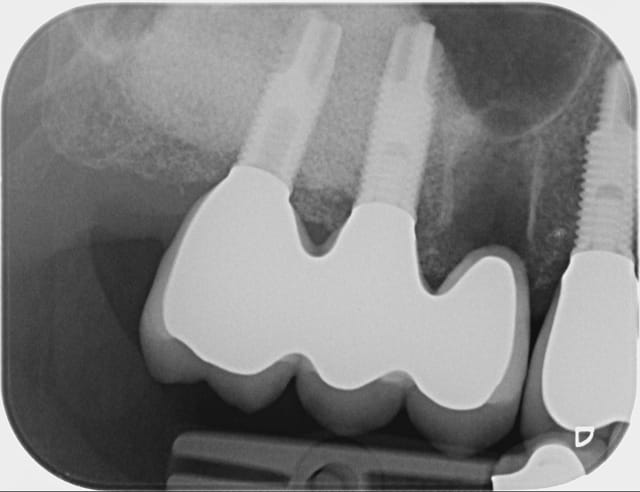

Bon alors revenons a cette 15.

On voit bien sur l'historique radio que la migration apicale a débuté entre janvier et mai 2014. Date à laquelle j'ai dû changer la 14.

J'aime bien les points de contacts assez serrés et là j'ai le souvenir qu'il était très costaud.

Je pense donc que la migration est dû a une compression de la 15 par effet de coin comme la supputer Shadow.

De toute manière maintenant elle ne bougera plus!